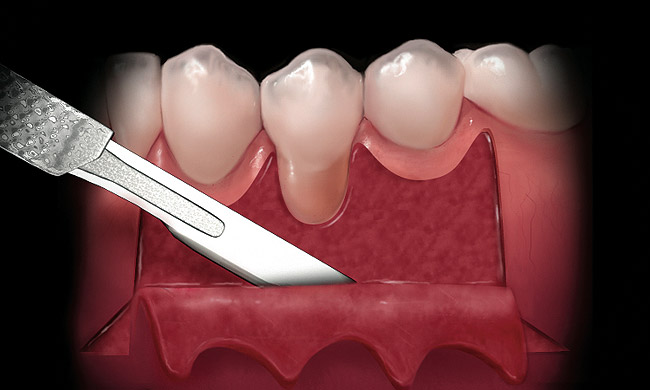

The Burrow’s triangle is then grasped by a tissue forceps and a split thickness dissection with a 15C blade is accomplished to remove this tissue (Figure 2).10 Using a 15C scalpel blade and holding the flap margins with tissue forceps, a split thickness flap is reflected past the mucogingival junction (Figure 3).

Figure 2  While grasping the tissue at the center of the Burrow’s triangle, a scalpel is used to excise it.

Figure 2

Figure 3  While grasping the flap margin with an Addison forceps, a scalpel is used to create a partial thickness flap.

Figure 3